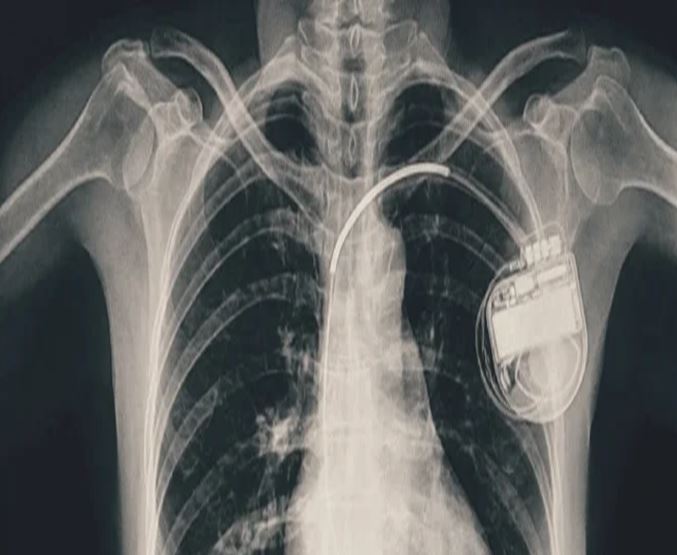

भोपाल। भोपाल मेमोरियल अस्पताल एवं अनुसंधान केंद्र (बीएमएचआरसी) के कार्डियोलॉजी विभाग ने एक दुर्लभ और चुनौतीपूर्ण चिकित्सा उपलब्धि हासिल की है। यहां 13 वर्ष की गैस पीड़ित आश्रित बालिका को इमरजेंसी में डुअल चेंबर पेसमेकर लगाकर उसकी जान बचाई गई। अब बालिका की हालत बेहतर है और उसे अस्पताल से छुट्टी दे दी गई है। यह प्रक्रिया सहायक प्रोफेसर डॉ. अमन चतुर्वेदी और उनकी टीम द्वारा सफलतापूर्वक की गई।

बीएमएचआरसी के कार्डियोलॉजी विभाग के सहायक प्रोफेसर डॉ. अमन चतुर्वेदी ने बताया कि यह मरीज जन्म से ही हृदय रोग से पीड़ित थी। तीन वर्ष की आयु में उसके दिल में छेद (congenital heart defect) का ऑपरेशन किया गया था। ऑपरेशन के बाद उसे हार्ट ब्लॉक हो गया यानी हृदय की धड़कन असामान्य रूप से धीमी हो गई। इसके कारण उसे चक्कर आना, आंखों के सामने अंधेरा छा जाना जैसी परेशानियां होने लगीं।हार्ट ब्लॉक की स्थिति में, बचपन में ही उसे एपिकार्डियल पेसिंग (epicardial pacing) डिवाइस लगाई गई। इस प्रक्रिया में पेसमेकर के तार हृदय की बाहरी सतह पर लगाए जाते हैं, जो आमतौर पर छोटे बच्चों में अपनाई जाती है, क्योंकि उनके हृदय का आकार छोटा होता है। इस डिवाइस की आयु लगभग 10 वर्ष होती है। डिवाइस की अवधि पूरी होने के बाद हाल ही में मरीज को फिर से वही लक्षण होने लगे। बीएमएचआरसी में जांच के बाद यह स्पष्ट हुआ कि अब उसे एक स्थायी और अधिक उन्नत पेसमेकर की आवश्यकता है। आपातकालीन स्थिति में टीम ने सफलतापूर्वक डुअल चेंबर पेसमेकर प्रत्यारोपित किया। इस जीवनरक्षक प्रक्रिया को अंजाम देने वाली टीम में कार्डियोलॉजी विभाग के सहायक प्रोफेसर डॉ. कपिलकांत त्रिपाठी, डॉ. नुपुर गोयल, मेडिकल ऑफिसर डॉ. अनुराग ठाकुर एवं अन्य सदस्य शामिल थे।

पेसमेकर एक छोटा उपकरण होता है, जो दिल की धड़कन को नियंत्रित करता है। यह दिल को सही गति से धड़कने में मदद करता है। सिंगल चेंबर पेसमेकर हार्ट के सिर्फ एक चेंबर को इलैक्ट्रिक सिग्नल देता है, जबकि डुअल चेंबर पेसमेकर दिल के दो भागों-ऊपरी (एट्रियम) और निचले (वेन्ट्रिकल) चेंबरों को दोनों को सिग्नल भेजता है, जिससे दिल की धड़कन और भी प्राकृतिक तरीके से चलती है। बच्ची के मामले में डुअल चेंबर पेसमेकर इसलिए लगाया गया क्योंकि उसकी स्थिति अधिक जटिल थी और बेहतर तालमेल के लिए दोनों चेंबर तक एकसाथ सिग्नल देना ज़रूरी था।